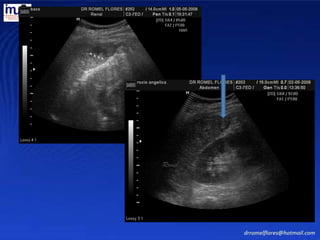

La posición adecuadapara valorar el bazo es en decúbito dorsal. Se debe valorar en varios grados de inspiración. Una inspiración moderada deprime la porción central del hemidiafragma izquierdo desplazando el bazo hacia abajo para poder visualizarlo.

La técnica delultrasonido no precisa preparación se explora en varias posiciones. Se obtienen cortes sagitales y transversales, en inspiración mantenida para que el bazo descienda y pueda ser mejor observado. Romel

El bazo eshomogéneo, con una ecogenicidad muy similar al hígado Romel

Se busca eneje mayor en la línea media axilar o axilar anterior. El eje longitudinal se mide en el corte donde presente más tamaño. El diámetro transverso es en la distancia mas ancha entre la convexidad y el hilio. Romel